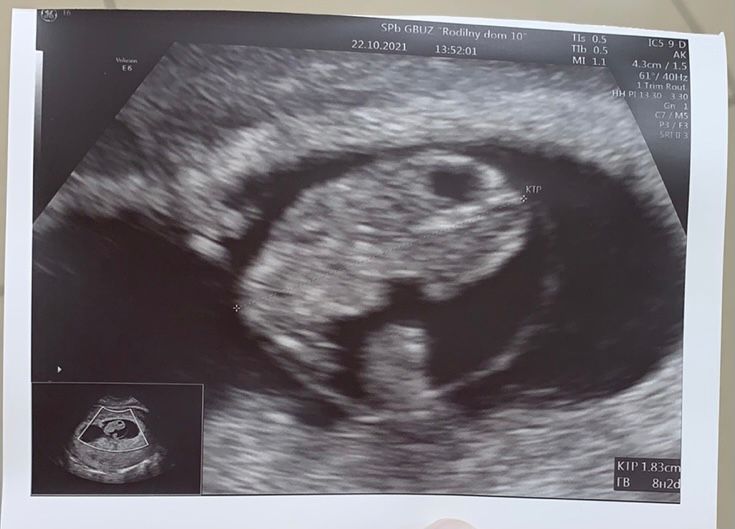

УЗИ 7+4. Хорошее!!

По размеру на 8+2: как по хгч опережал, так и по ктр. Видимо, прицепился рано, да и перенос был на 17 дц.

КТР 18,3, ЧСС 167, ПЯ 37,7, ЖМ 4,1.

Прикрепился по задней стенке. Гематом-отслоек-тонуса нет.